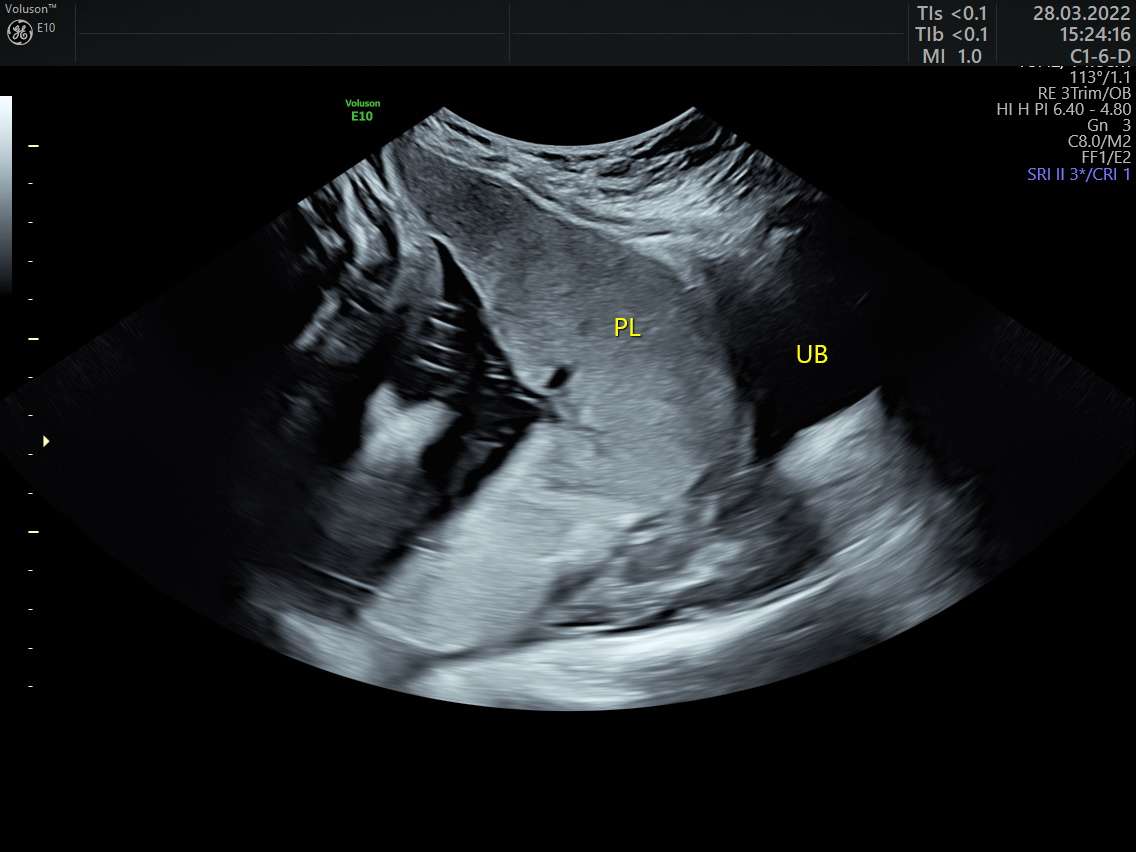

Woman of 45 years, with two...